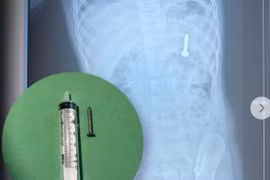

Do dạ dày trẻ còn nhiều thức ăn chưa được tiêu hóa, các bác sĩ phải mất khá nhiều thời gian, tập trung cao độ để dò tìm và tiếp cận dị vật một cách an toàn. Cuối cùng, đồng xu được gắp ra thành công, giúp bệnh nhi thoát khỏi nguy hiểm.

22-gio-dem.jpg

Đồng xu được lấy ra an toàn - Ảnh BVCC